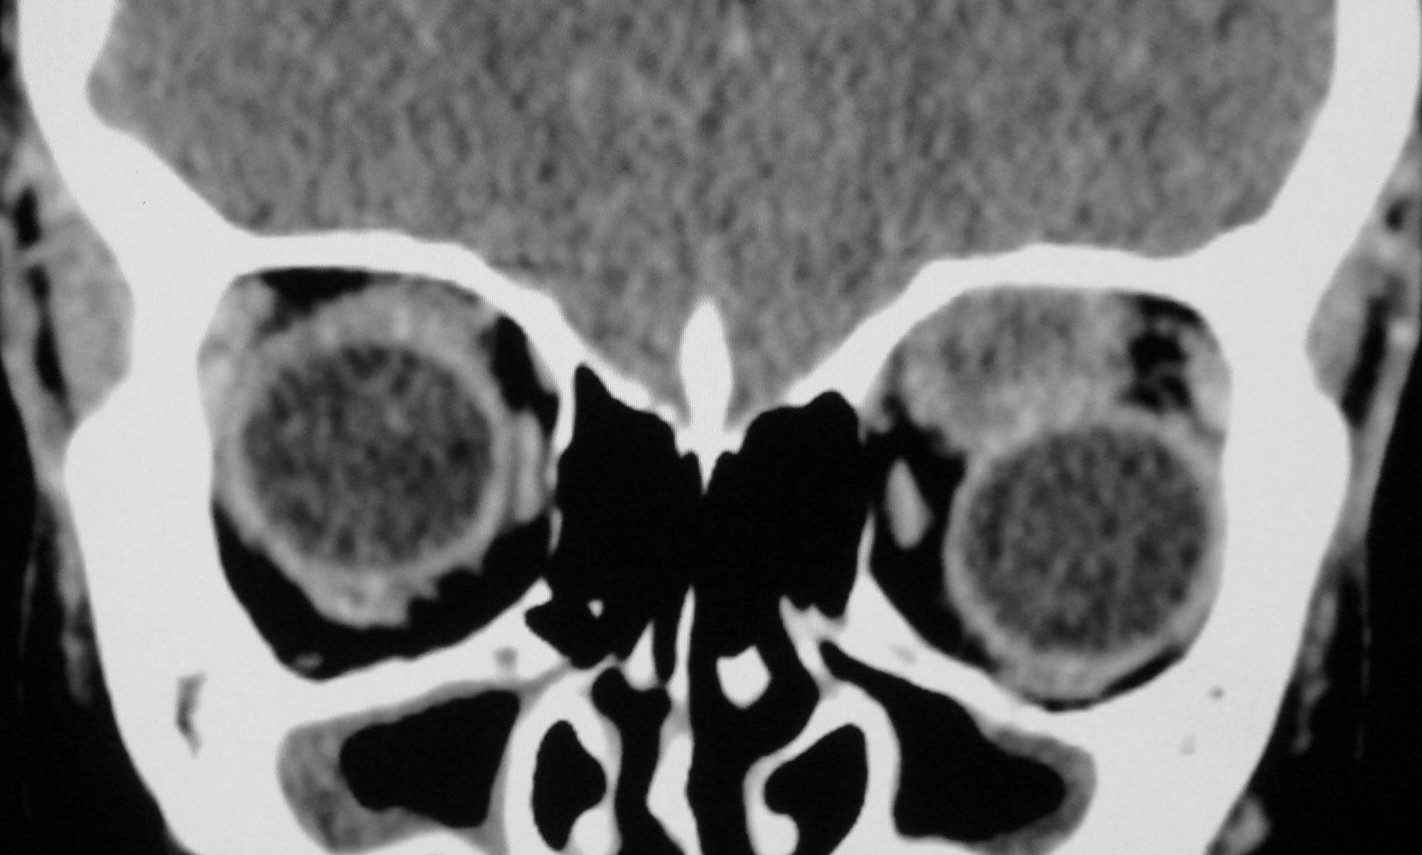

The ocular involvement of the cysticercosis is a rare entity involving eyelids, extraocular muscles, orbit, conjunctiva, anterior chamber, uvea, retina, vitreous and optic nerve. All the extraocular muscles are involved in myocysticercosis. Ultrasonography and Computed tomography are the imaging modalities for evaluation of ocular cysticercosis. The patients can be treated with systemic steroids and albendazole; however surgical excision is the treatment of choice. We report a rare case of extraocular myocysticercosis in nine years old boy diagnosed on ultrasonography and computed tomography.